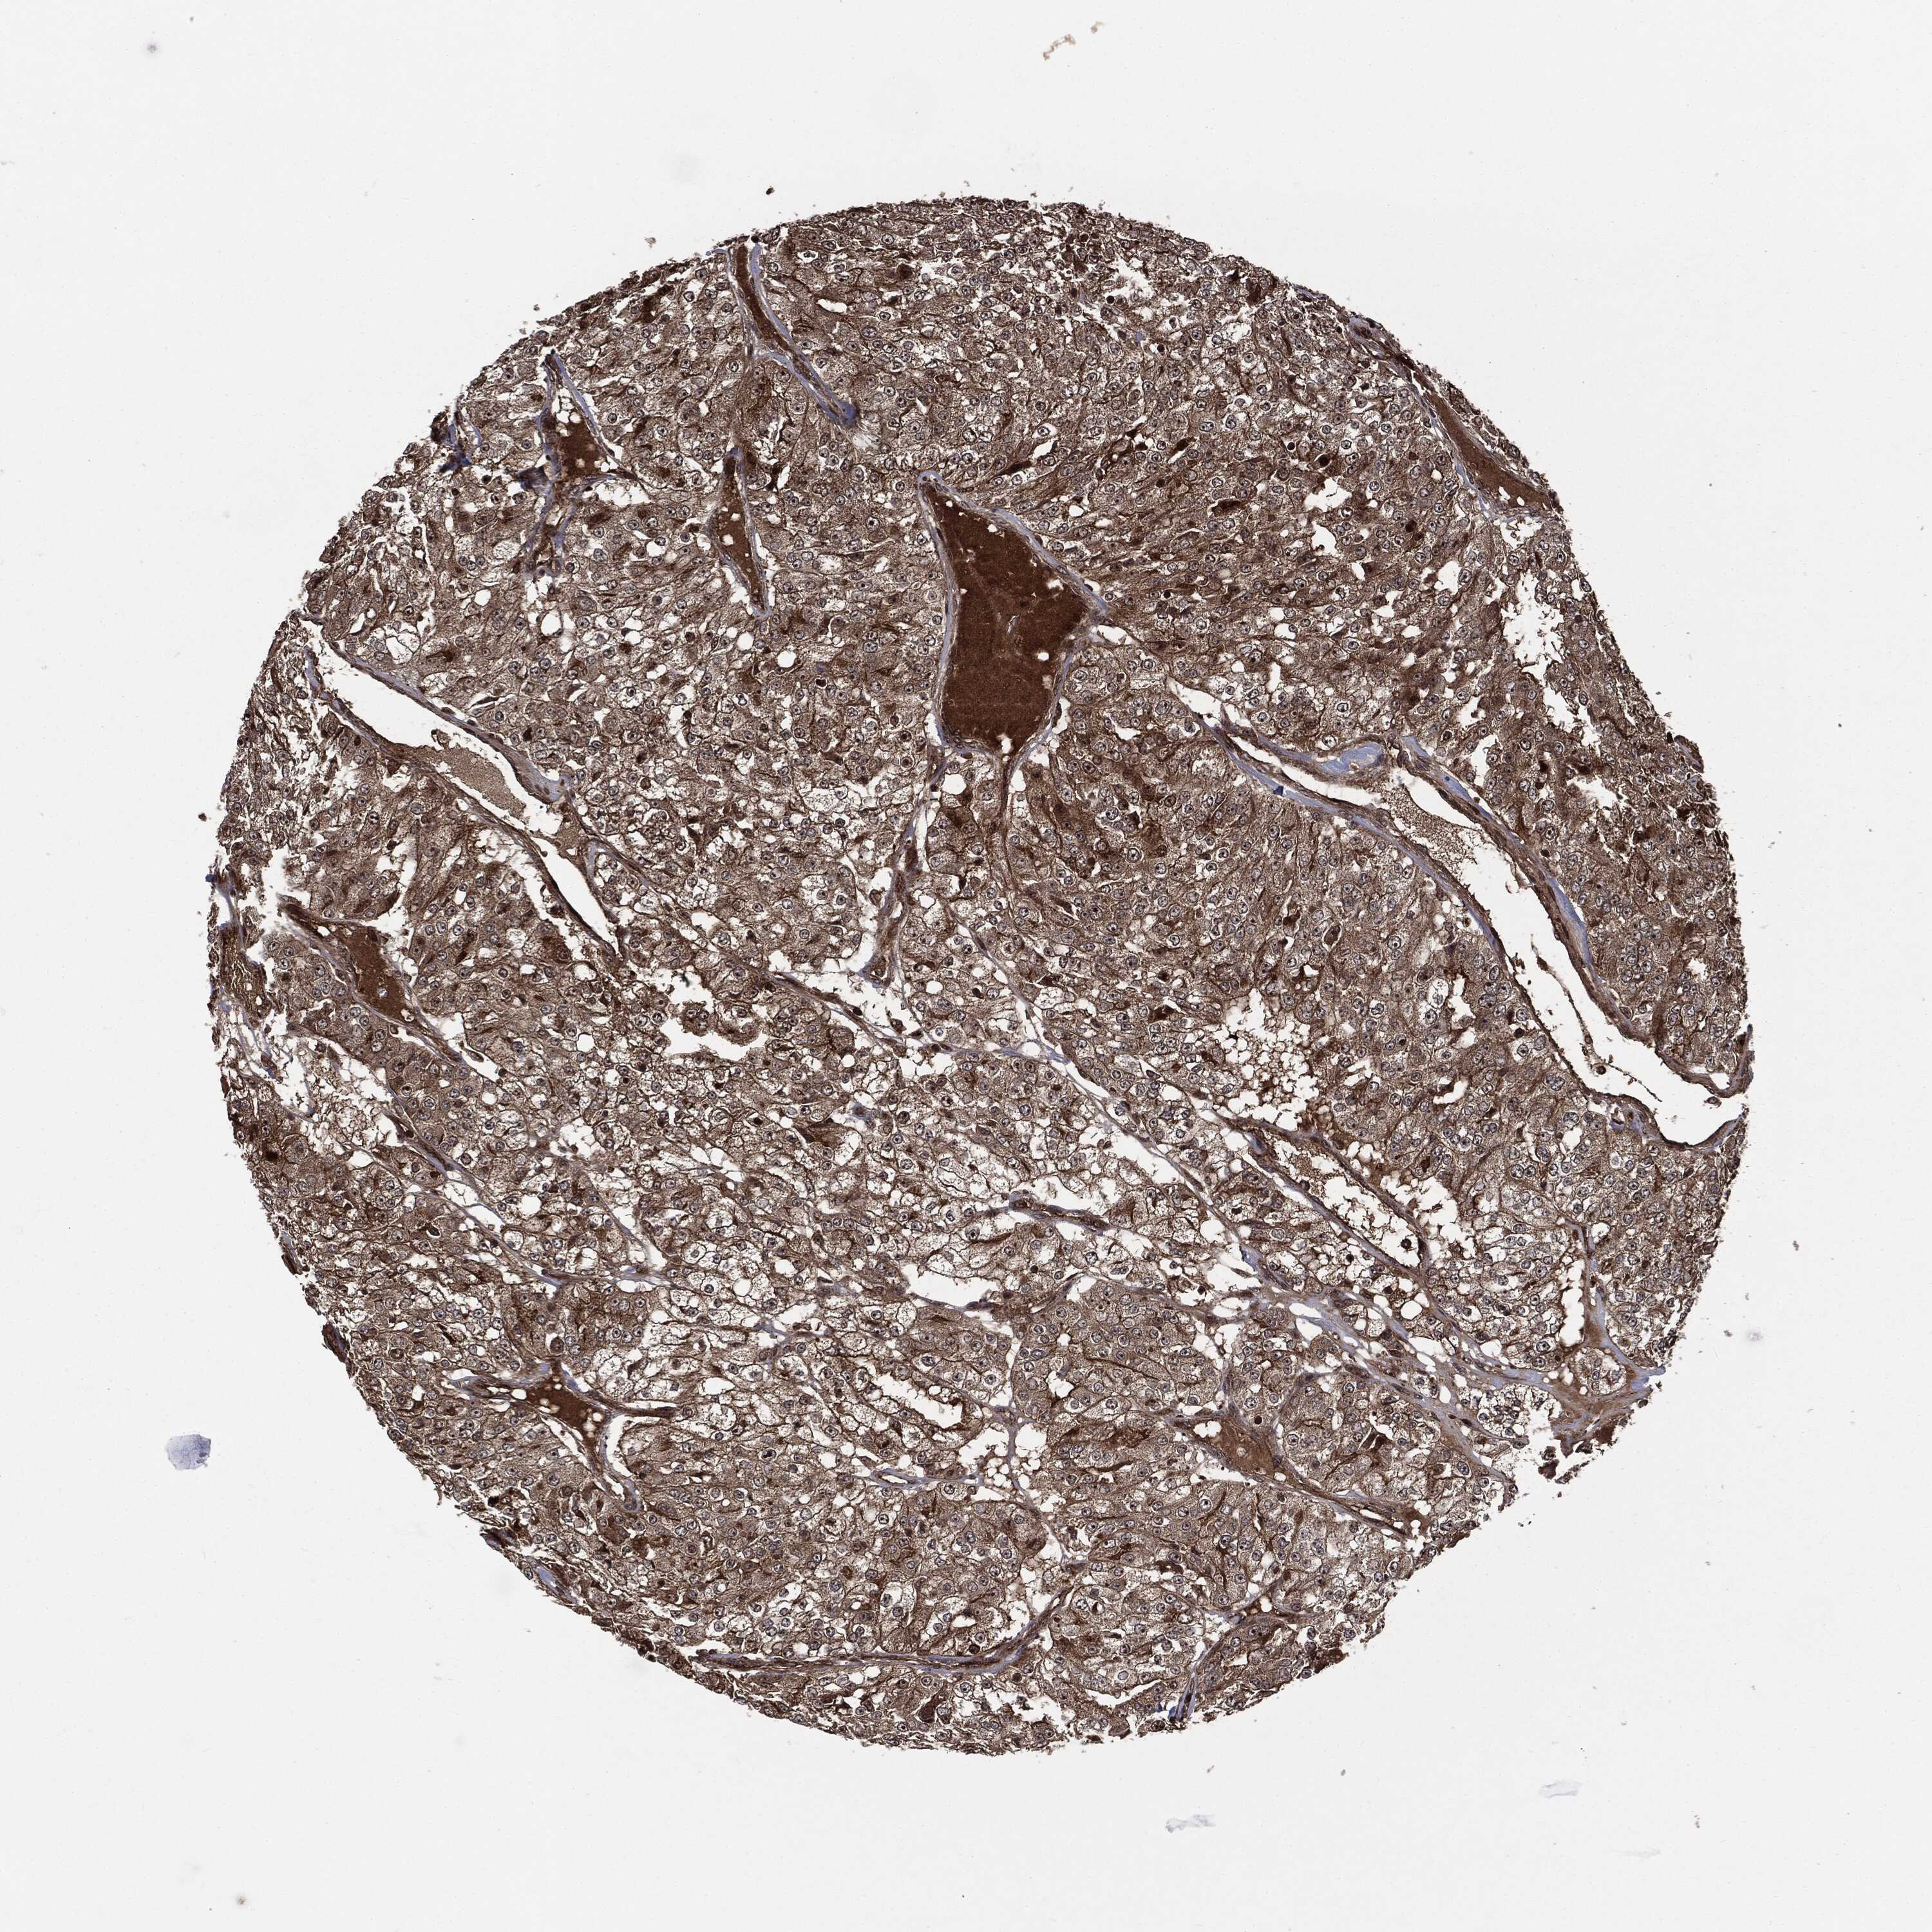

CANCER RENAL CANCER Show tissue menu

KICH TCGA KIRC TCGA KIRC VALIDATION KIRP TCGA PROTEIN RCC CPTAC PROTEIN EXPRESSION